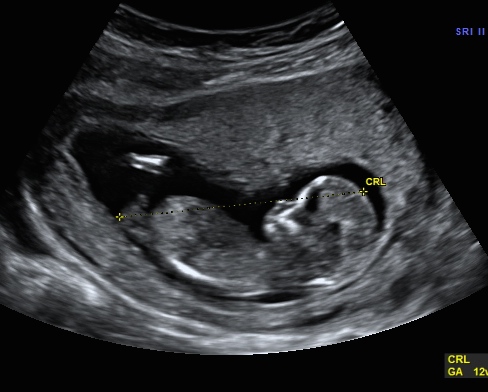

Hi ladies! Just wondering if you will agree with my u/s tech! Any feedback is appreciated! :D Thanks in advance!